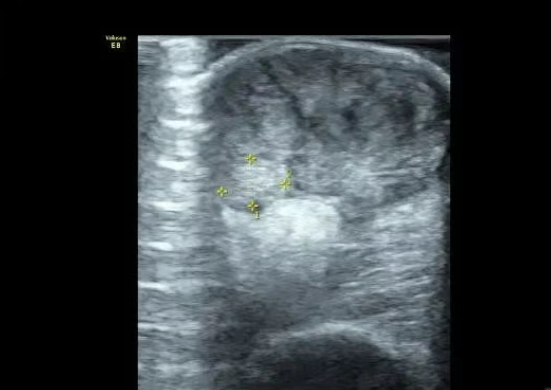

患者女,45岁。因现双侧跟腱肿物多年,2年前手术切除,病理诊断黄色瘤,目前术后复发来就诊。肉眼可见跟腱不均匀增粗,双侧髌腱、双手伸肌腱等多处结节状病变。 超声表现:上述肌腱内低回声包块,呈对称性生长,边界不清,形态欠规则,内部回声不均,以跟腱最为明显,正常跟腱可见,呈偏心性,与周围团块有一定分界,但分界欠清晰,CDFI:内未见明显血流信号。结合病史考虑腱黄色瘤。

腱黄色瘤也叫黄素瘤,是指脂肪组织沉积在皮肤和肌腱内的一些富含脂肪的结节或丘疹,外观呈橙黄色,故称黄色瘤,是一种罕见的良性肿瘤,可发生于人体各个部位,但最常发生在跟腱、肘关节、膝关节、指间关节等伸肌腱处。也可发生在皮肤真皮层,导致皮肤损害形成结节或丘疹,皮损好发于关节伸侧皮肤如肘、膝;还可发生在臀部、眼睑等部位,称皮肤黄色瘤。 黄色瘤的发病机制还不是完全清楚,发病原因主要是与原发性(家族性)或继发性高脂血症有关。 主要包括以下几个发病类型: 1、原发性黄色瘤:分为先天性遗传性和非先天性遗传性。先天性遗传性多有高脂蛋白血症史或脂蛋白代谢水平异常等症状(后面重点介绍)。而非先天性黄色瘤多于饮食,生活习惯,药物因素等有关。 2、继发性黄色瘤:多继发于一些慢性代谢性疾病,如糖尿病、甲状腺功能减退者、动脉粥样硬化等。该类患者大多数有甘油三酯,胆固醇和脂蛋白水平的升高。 3、血脂正常性黄色瘤:该型发病时间较早,多发于10岁以下儿童。如幼年性黄色瘤、播散性黄色瘤、血脂正常性黄色瘤等。还有部分多与物理性或化学性刺激有关。考虑其原因可能与刺激因素和自身反复动作刺激局部组织增殖,脂蛋白和胆固醇被组织细胞吞噬所致。该类患者血脂未见明显异常,也归为血脂正常性黄色瘤。 病理:腱黄色瘤病理特点为含脂质的巨噬细胞、炎性细胞和增生的胶原纤维形成黄色瘤样组织。 临床表现:肌腱黄色瘤好发于跟腱、肘关节、膝关节及指间关节等关节的伸肌腱部位无痛性包块,以跟腱最为常见。早期轻者表现为跟腱的增厚,呈梭形增粗。跟腱病变常委双侧性和对称性,多累及跟骨的附着处,极少部分可引起跟腱的断裂。 超声表现:超声检查是诊断跟腱黄色瘤的首选。较轻的病例表现为跟腱的增厚,在男性跟腱前后径>7mm,女性中跟腱的厚度>6mm,同时在跟腱内可见多发性在灶状低回声病灶。严重的病例可在跟腱内出现较大的低回声包块,包块内部回声不均,通常伴有不规则的衰减。 鉴别诊断:1、痛风;2、慢性肌腱变性;3、肌腱炎;4、感染;5、肿瘤。 治疗:目的为改善功能及外观,减轻患者局部疼痛。对于无症状者是否手术干预存在争议。但是,当患者存在局部疼痛或者踝关节功能障碍并且影响日常生活时,应考虑手术治疗。